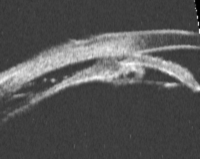

睫状体在手术或外伤的情况下,可能发生房角后退、睫状体截离(图1、表1)、睫状体疤痕或前膜(前部PVR)、睫状体脱离(图2)/脉络膜脱离、睫状体水肿、睫状体缺损等并发症,影响睫状体的正常功能,使房水分泌减少,眼压降低。

图1. 睫状体截离:睫状体与巩膜突及巩膜之间出现裂隙,睫状体上腔与前房沟通